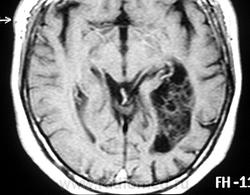

ГМ. Субэпендимома 2. +

Субэпендимома